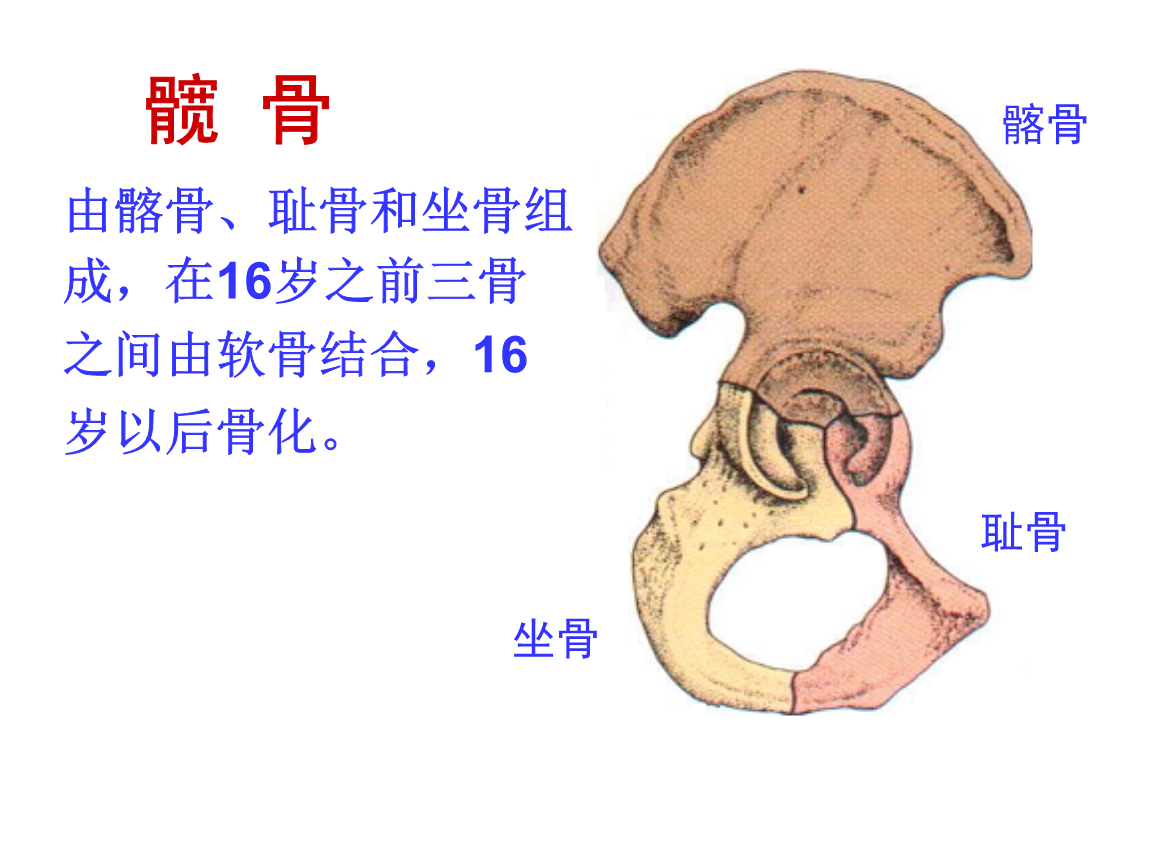

系解本科课件第八版《运动系统》髋骨.ppt

图片尺寸1152x864